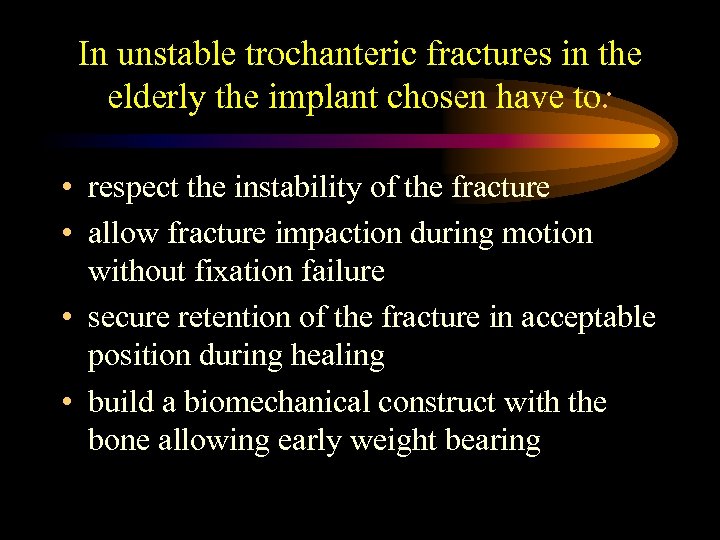

In unstable trochanteric fractures in the elderly the implant chosen have to: • respect the instability of the fracture • allow fracture impaction during motion without fixation failure • secure retention of the fracture in acceptable position during healing • build a biomechanical construct with the bone allowing early weight bearing

In unstable trochanteric fractures in the elderly the implant chosen have to: • respect the instability of the fracture • allow fracture impaction during motion without fixation failure • secure retention of the fracture in acceptable position during healing • build a biomechanical construct with the bone allowing early weight bearing

In unstable trochanteric fractures in the elderly the implant chosen have to: • respect the instability of the fracture • allow fracture impaction during motion without fixation failure • secure retention of the fracture in acceptable position during healing • build a biomechanical construct with the bone allowing early weight bearing

In unstable trochanteric fractures in the elderly the implant chosen have to: • respect the instability of the fracture • allow fracture impaction during motion without fixation failure • secure retention of the fracture in acceptable position during healing • build a biomechanical construct with the bone allowing early weight bearing